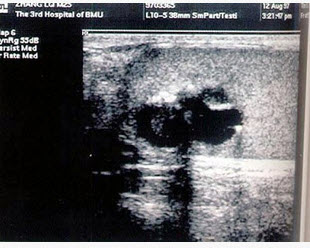

[单选题]患者男,21岁,发现睾丸无痛肿块,局部不规则,结合超声图像,最可能的诊断是()。A . 精原细胞瘤B . 睾丸畸胎瘤C . 精母细胞瘤D . 睾丸腺癌E . 睾丸囊肿